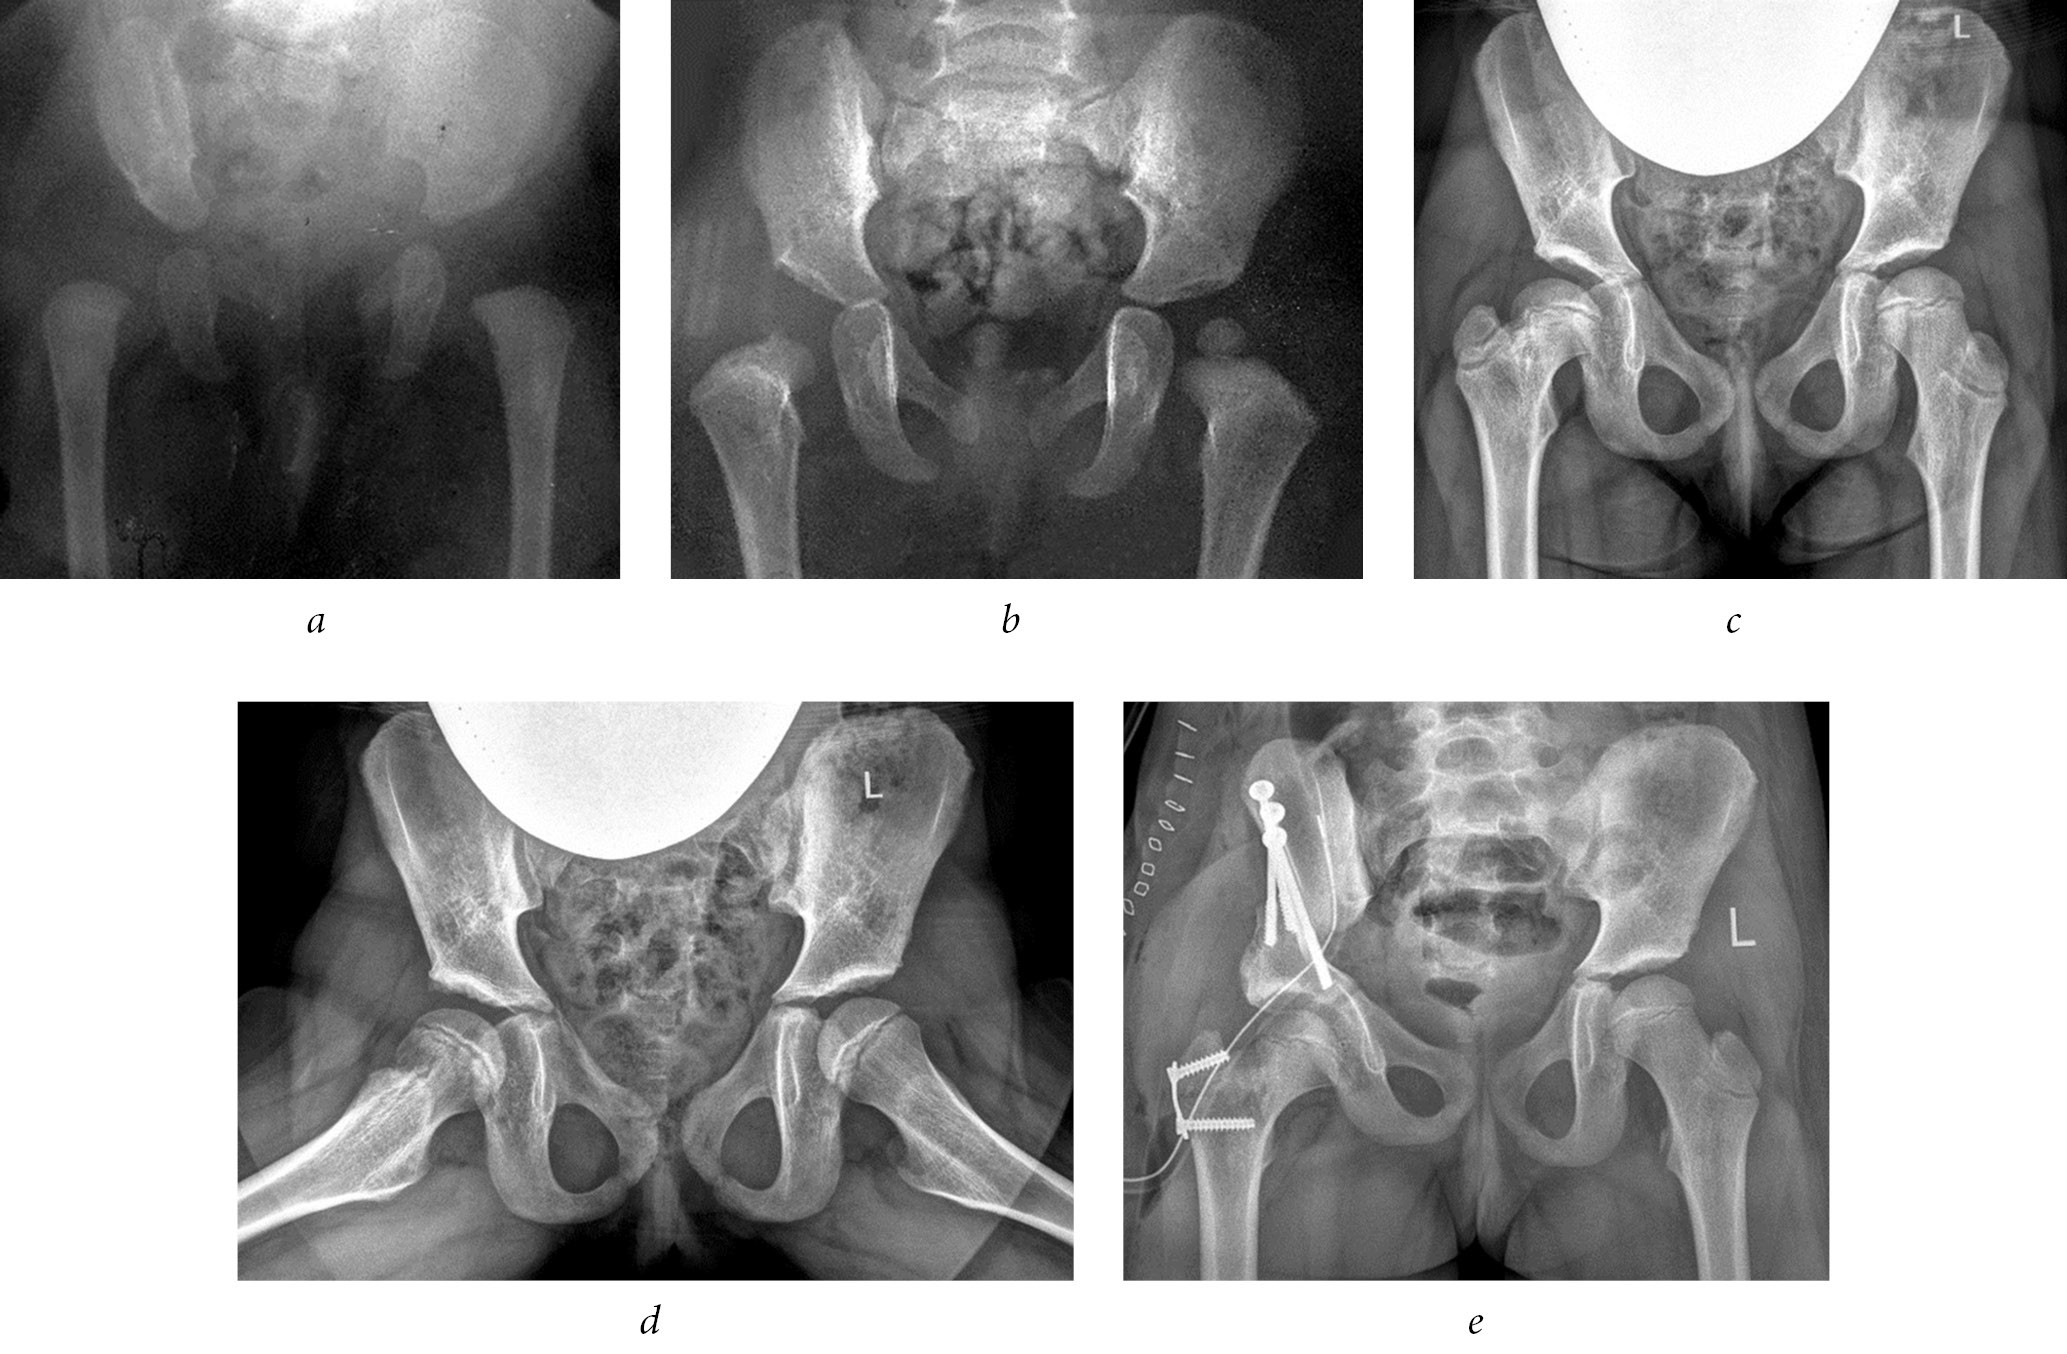

To exclude displacement of the greater trochanter, adherence to bed rest, or use of ambulation support in the postoperative period, before the destruction of the growth zone, the greater trochanter was fixed to the femur using an eight-shaped plate with screws or a cortical screw with a washer. The eight-shaped plate was installed from the lateral surface of the hip, and the cortical screw was inserted from the superior lateral parts of the greater trochanter toward the lesser trochanter parallel to the intertrochanteric line of the femur (Figs. 1, 2) [19].

Fig. 1. Radiographs of patient U (7 years old) diagnosed with congenital dislocation of the right hip, condition after conservative treatment, and residual developmental hip dysplasia. Complications of aseptic necrosis of the femoral head include femoral neck shortening, formation of Kalamchi type II deformity, and high position of the greater trochanter: a, at 4 months old; b, at 1 year old; c, d, at 7 years old, before surgery; e, immediately after iliac pelvic osteotomy and trochanteric epiphysiodesis on the right